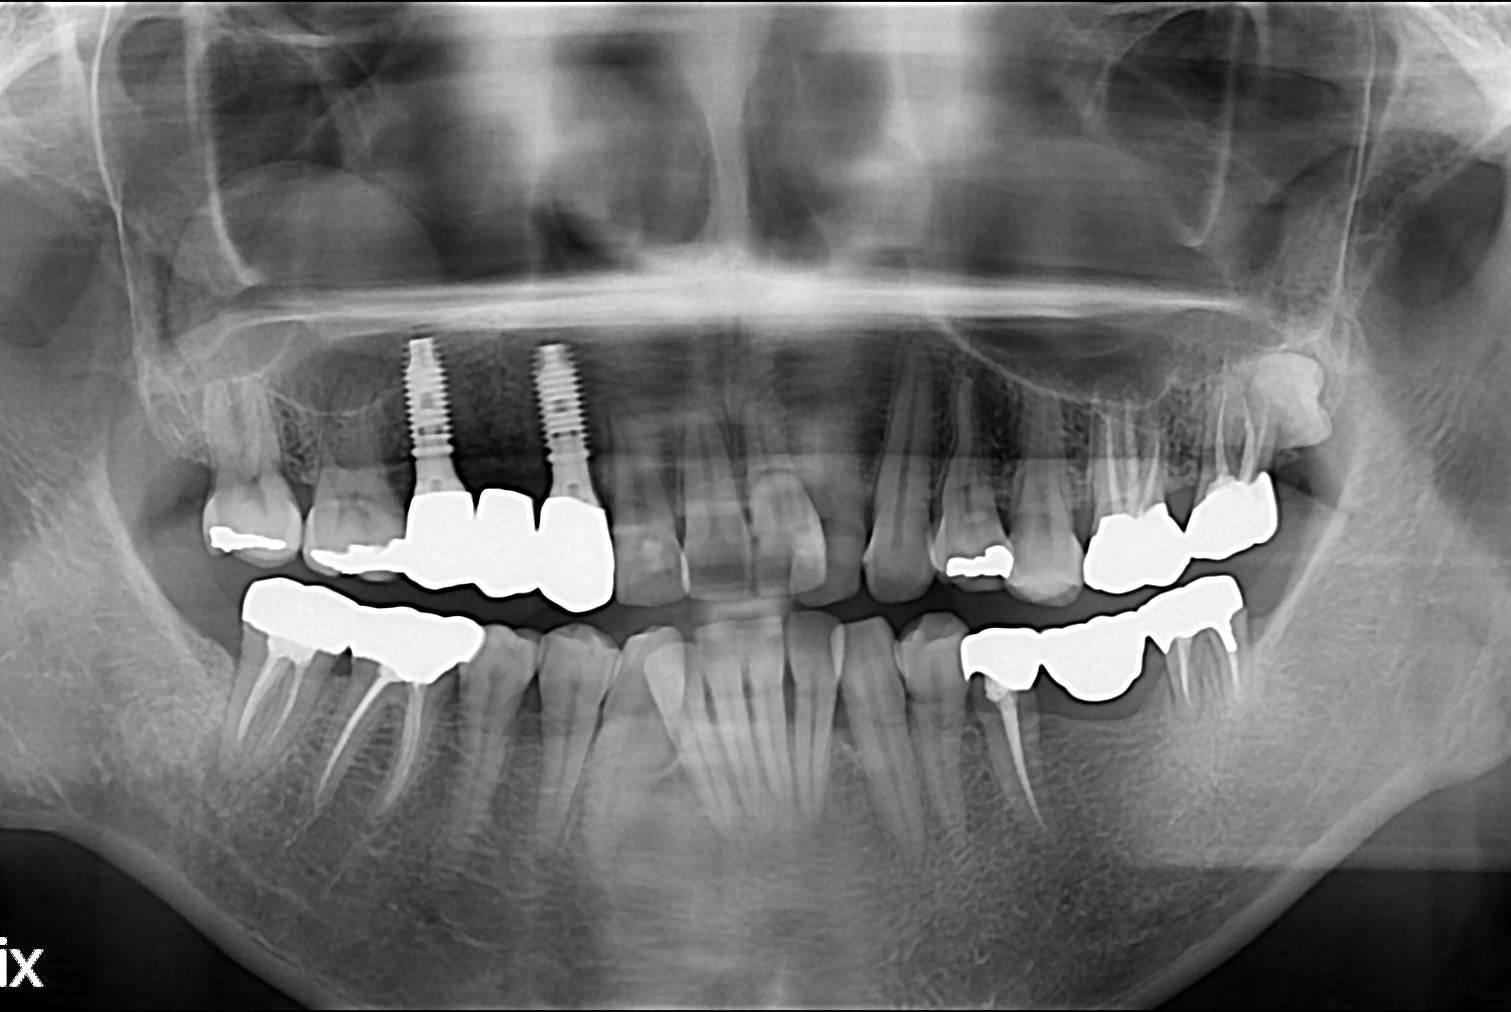

치료후 : 2019-03-27

세종치과는 많은 환자와 다양한 케이스를 바탕으로 항상 편안한 임플란트 수술을 제공하고자 노력하고,

오래동안 튼튼히 쓸 수 있는 임플란트 수술을 가장 큰 목표로 삼고 있습니다